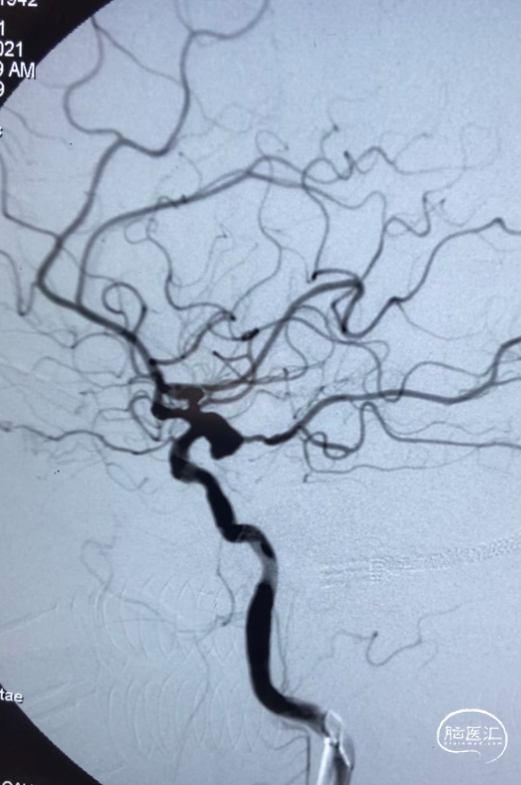

术前影像

栓塞过程

支架半释放先填入两枚弹簧圈,再将支架完全释放,填入四枚Jasper®SS弹簧圈。

术后即刻影像

本病例为基底动脉中段不规则破裂动脉瘤,采取支架辅助弹簧圈栓塞,Jasper®SS弹簧圈在微导管内推送过程中感觉相对更顺滑,Jasper®SS弹簧圈进入动脉瘤时也能根据其金属的记忆形状自然盘绕顺应性较好。